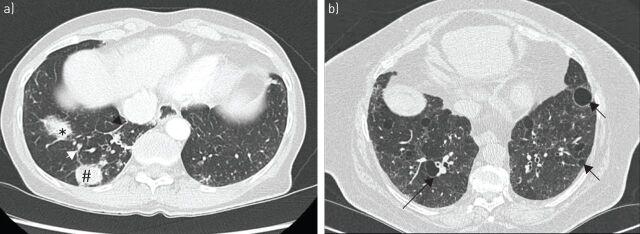

In 9-20% of cases, Sjögren's syndrome is associated with various respiratory symptoms. The most typical manifestations are chronic interstitial lung disease (ILD) and tracheobronchial disease. The most common manifestation of ILD is nonspecific interstitial pneumonia in its fibrosing variant. Other types of ILD, such as organising pneumonia, usual interstitial pneumonia and lymphocytic interstitial pneumonitis, are rare. Their radiological presentation is less distinctive, and definitive diagnosis may require the use of transbronchial or surgical lung biopsy. Corticosteroid therapy is the mainstay of ILD treatment in Sjögren's syndrome, but the use of other immunosuppressive drugs needs to be determined. ILD is a significant cause of death in Sjögren's syndrome. Tracheobronchial disease is common in Sjögren's syndrome, characterised by diffuse lymphocytic infiltration of the airway. It is sometimes responsible for a crippling chronic cough. It can also present in the form of bronchial hyperresponsiveness, bronchiectasis, bronchiolitis or recurrent respiratory infections. The management of these manifestations may require treatment for dryness and/or inflammation of the airways. Airway disease has little effect on respiratory function and is rarely the cause of death in Sjögren's syndrome patients. Rare respiratory complications such as amyloidosis, lymphoma or pulmonary hypertension should not be disregarded in Sjögren's syndrome patients.

在9%至20%的病例中,干燥综合征与多种呼吸道症状相关。最典型的表现是慢性间质性肺疾病(ILD)和气管支气管疾病。ILD最常见的表现是纤维化型非特异性间质性肺炎。其他类型的ILD,如机化性肺炎、寻常型间质性肺炎和淋巴细胞间质性肺炎则较为罕见。它们的影像学表现不太具有特征性,明确诊断可能需要进行经支气管或外科肺活检。糖皮质激素治疗是干燥综合征中ILD治疗的主要手段,但其他免疫抑制药物的使用需要确定。ILD是干燥综合征患者死亡的重要原因。气管支气管疾病在干燥综合征中很常见,其特征是气道弥漫性淋巴细胞浸润。它有时会导致严重的慢性咳嗽。它也可能表现为支气管高反应性、支气管扩张、细支气管炎或反复呼吸道感染。这些表现的管理可能需要对气道干燥和/或炎症进行治疗。气道疾病对呼吸功能影响较小,很少是干燥综合征患者死亡的原因。干燥综合征患者不应忽视罕见的呼吸道并发症,如淀粉样变性、淋巴瘤或肺动脉高压。